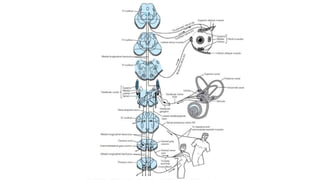

• The brainstem, cerebellum, and peripheral labyrinths - all supplied by

the vertebrobasilar arterial system.

• #14 Midbrain – pons – medulla = brainstem cerebellum